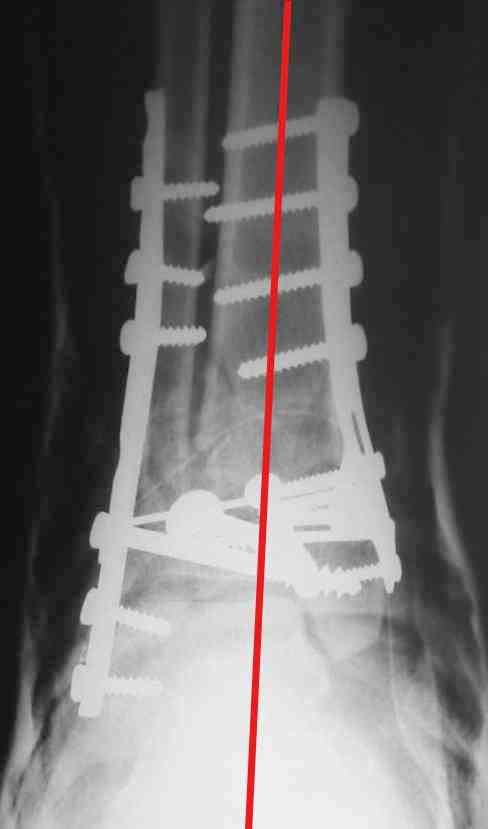

OK, Dr Driagin, Ja operiroval bolnogo po Vashemu, hotia sam ni ochen' ubezden' v itom, t.k. bolnoi otkazalsa na proch' ot ex.fix, ja emu sdelal ORIF + Kostnia plastika, snimky prelogiottsa,

Очень прилично получилось, но мне показалось, что винты на 4,5 мм.Это принципиально винты используются 3,5 и 4,0 мм. И проекцию прямую бы переделать. С уважением Дрягин

ДВ> Очень прилично получилось, но мне показалось, что винты на 4,5 мм.Это

ДВ> принципиально винты используются 3,5 и 4,0 мм.

А чем чревато использование обычных кортикальных винтов 4,5 мм с не-LCP пластинками?

На представленном снимке видно, что эпифиз смещен латерально.

Сейчас с этим ничего не сделать, похоже.

Пластина лист клевера есть в варианте DCP -динамическая компрессирующая пластина.В ней все отверстия круглые,развальцованные отверстия под винт 3,5, чтобы шляпка винта не торчала.Винты 4,5 тоже проходят в эти отверстия, но шляпка не погружается.Могут быть проблемы с мягкими тканями.Пластина LCP -пластина с блокированием.В каждом отверстие пластины нарезана резьба и на шляпке винта такая же.Получается блок винт-пластина-кость.Очень крепко.Первоначально она готовилась для остеопороза, много лет в Давосе её разрабатывали.Я видел там первые образцы ещё в 1995 году, а начали они в 80-годах.Насчёт оси по рентгенограмме пока не согласен пусть сделают хорошую, правильную прямую проекцию.С уважением Дрягин

Однозначно сказать сложно.Расстояние между тараном и медиальной лодыжкой меньше чем между тараном и крышей большеберцовой кости.Это может быть за счёт не правильной укладки.Пока не отчаиваетесь.Главное вы поняли принцип.Сделайте несколько проекций прямых и посмотрим.Для всех интересно.С уважением

Мне кажется, что все конечно далеко от идеала. Сложный перелом. Есть ощущение, что малоберцовая кость (ключ!) фиксирована с ротацией и удлинением. Снимки конечно необходимо сделать в правильных проекциях и без гипса...

В голеностопном суставе обязательны 3 стандартные ренгенологические проекции: прямая, латеральная и мортиз. Без них невозможно трактовать состояние голеностопа.

Применение шурурпов 4.5 мм и более толстых пластин крайне недопустимы. Рекомендуется низкопрофильные, контурированные пластины с шурупами 3.5 мм, а иногда те же 3.5 шурупы но с головкой 2.7 мм.